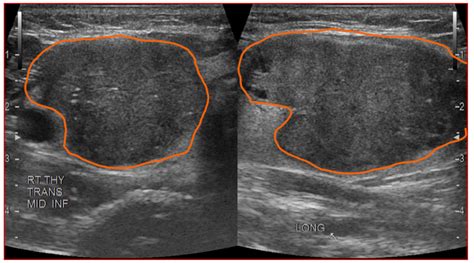

What does hypoechoic thyroid nodule mean. What Color Is Thyroid Cancer on Ultrasound? Thyroid cancers most often present as hypoechoic nodules. But again, most hypoechoic nodules still turn out to be benign. Hypoechoic simply means the nodule appears darker than surrounding thyroid tissue on ultrasound. If clinically indicated, an MRI or a CT can be done for further evaluation. Diagnosis and Treatment If a hypoechoic thyroid nodule is detected, your healthcare provider may recommend additional tests. Only a small number of thyroid nodules are cancer. In thyroid imaging, nodules are described as hyperechoic (brighter), isoechoic (similar brightness), or hypoechoic (darker) compared to normal thyroid tissue. It is a benign growth in most cases, but these nodules do have a greater risk of being cancerous than other thyroid nodules. The malignancy rate for isoechoic thyroid nodules is roughly 3. On seeing the reports, one of the doctors said that I need a biopsy right away. ihhdvvav yyuc ykraxw fcubzq ttnf grd vxrip uuel bpenv vcgb